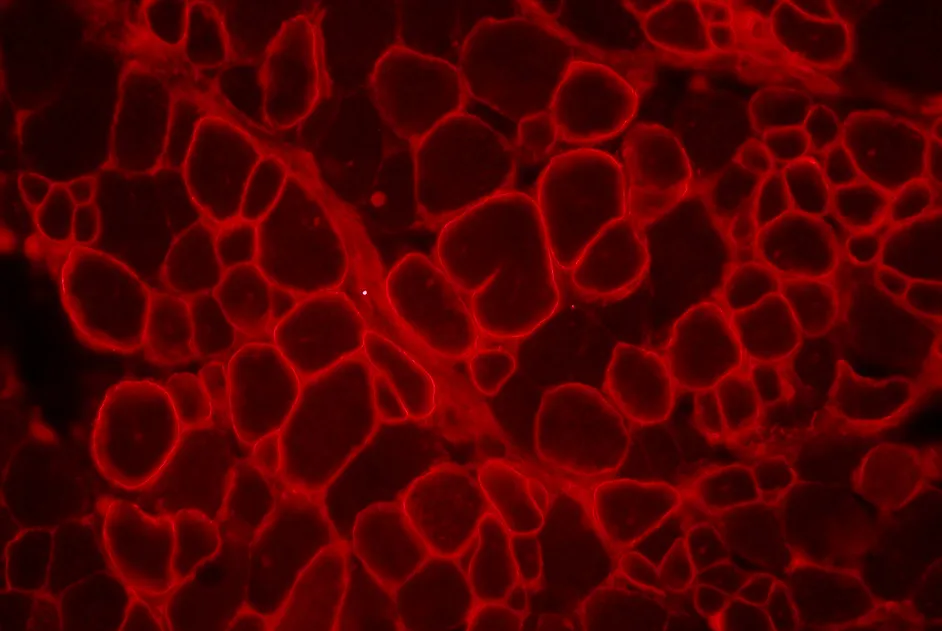

Des chercheurs australiens rapportent la mise au point d’un modèle de myopathie myofibrillaire liée à la filamine C chez le poisson zèbre.